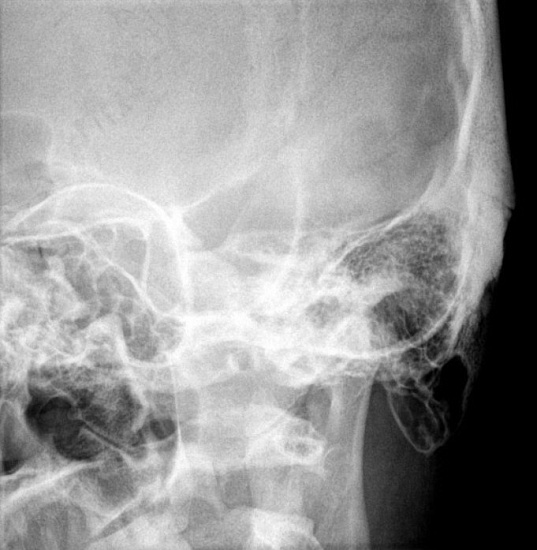

Рентгенография сосцевидных отростков – важный метод прицельного исследования сосцевидных отростков.

Диагностическая услуга выполняется в одной/двух проекциях. Сосцевидные отростки – выступы костей, которые расположены на боковых сторонах позвонках. Они играют важную роль в поддержании стабильности позвоночника и защите спинного мозга.